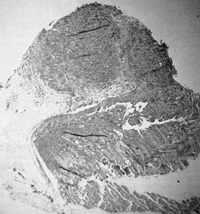

Fig. 4. Morphology of „immortalized cell line induced from normal human blood after infection by Ganot IVH and EBV positive ( Magnification 1000 x )

Fig,5. B-Cell lymphoma of nude mouse induced by injection of mouse with cells induced to grow by GaLVH Cells are human as determined by karyotype analysis. (From P Markham, F Ruscetti. Z. Salahuddin, R Gallagher. and R. Gallo. in press)